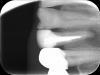

Ico Опубликовано 8 ноября, 2013 Поделиться Опубликовано 8 ноября, 2013 (изменено) 2.jpg1.jpg3.jpg надо сохранять)Только после успешни резухи! Изменено 8 ноября, 2013 пользователем Ico Ссылка на комментарий

Ildarad Опубликовано 8 ноября, 2013 Поделиться Опубликовано 8 ноября, 2013 Только после успешни резухи!Привет Паш!.консервативни получилось) стенки только тонкие очень, не треснул бы Ссылка на комментарий

Ildarad Опубликовано 8 ноября, 2013 Поделиться Опубликовано 8 ноября, 2013 Прикольно!!Только не эстетично Пока латералил думаю пару штифтов оторвал и за апекс ушли) да, картинка самому не нравится. А динамика нравится, 8 мес) Ссылка на комментарий